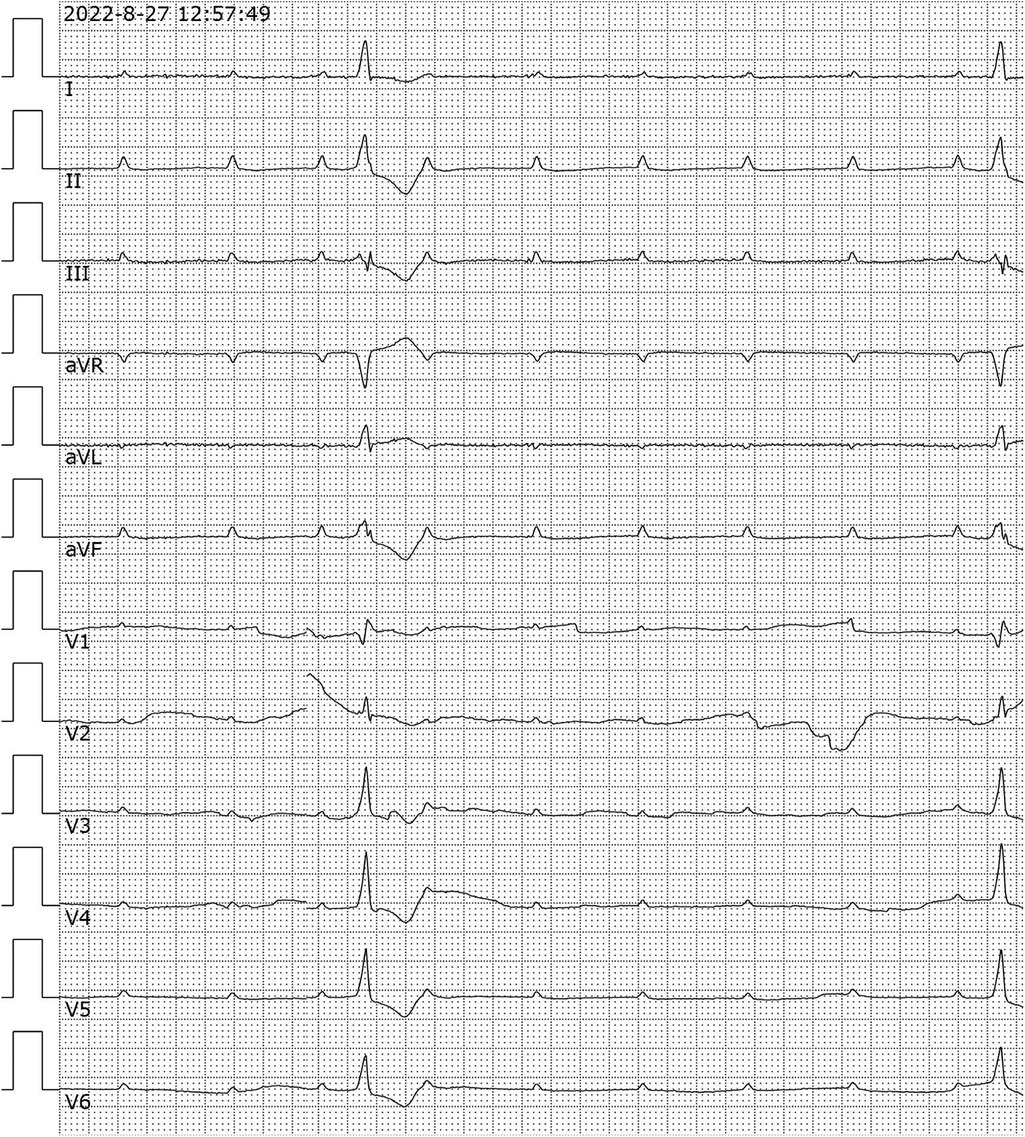

Upon admission, the patient had sudden limb twitch again, loss of consciousness, accompanied by urinary incontinence. The limb twitch lasted for about 2 min and then the patient stopped by herself. Subsequent to the patient regaining consciousness, he exhibited symptoms including fatigue and dizziness, accompanied by abdominal pain and distension. However, no obvious abnormality was found in chest and abdominal CT examination. Thus, emergency department was considered for “epilepsy” and sodium valproate was given epilepsy control. During the observation period, the patient had another episode of unconsciousness, with his eyes turned upside down, and woke up after 10 s. ECG monitoring indicates a drop in heart rate to 30 beats/min with premature ventricular beats, Blood pressure Monitoring indicates a rapid drop in blood pressure. A bedside electrocardiogram suggests a high atrioventricular block (Figure 1), Laboratory tests showed: WBC 6.8 × 109/L, CRP 18.7 mg/L, ALT 181 U/L, LDH 508 U/L, cTnI 14 ng/ml, CK 629 U/L, Lactate 2.98 mmol/L, NT-proBNP 3,940 ng/L. Considering the patient's critical condition, she was admitted to the intensive care unit(ICU) for further treatment.

Figure 1. Analysis of electrocardiogram. 12-lead electrocardiogram showed high atrioventricular block. aVR, Augmented Vector Right; aVL, Augmented Vector Left; aVF, Augmented Vector Foot.